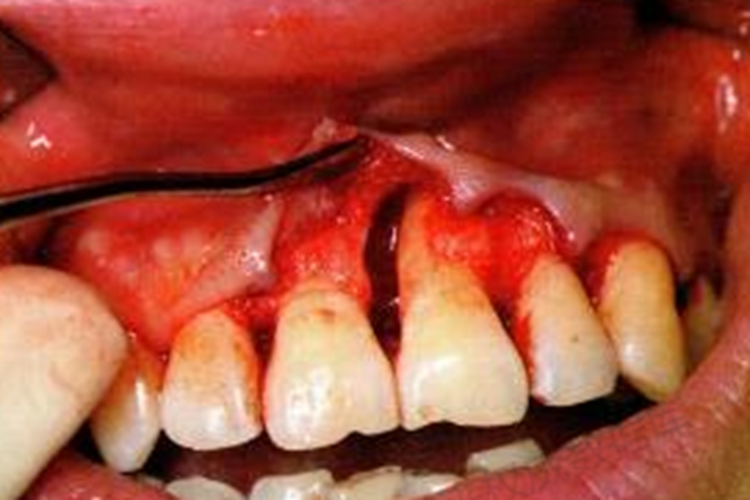

牙槽骨吸收的局部因素是慢性炎症、咬合创伤,其中慢性炎症是骨破坏的常见原因。当牙龈中的慢性炎症向深部牙周组织扩展达到牙槽骨附近时,可引发骨吸收,或使骨小梁吸收变细,骨髓腔增大。

牙槽骨吸收应尽早、尽快控制牙周炎症,防止牙槽骨吸收继续进展。控制炎症后再考虑对已经形成的骨缺损进行修复性治疗,以手术为主,包括骨成形、骨移植及骨组织再生术等。